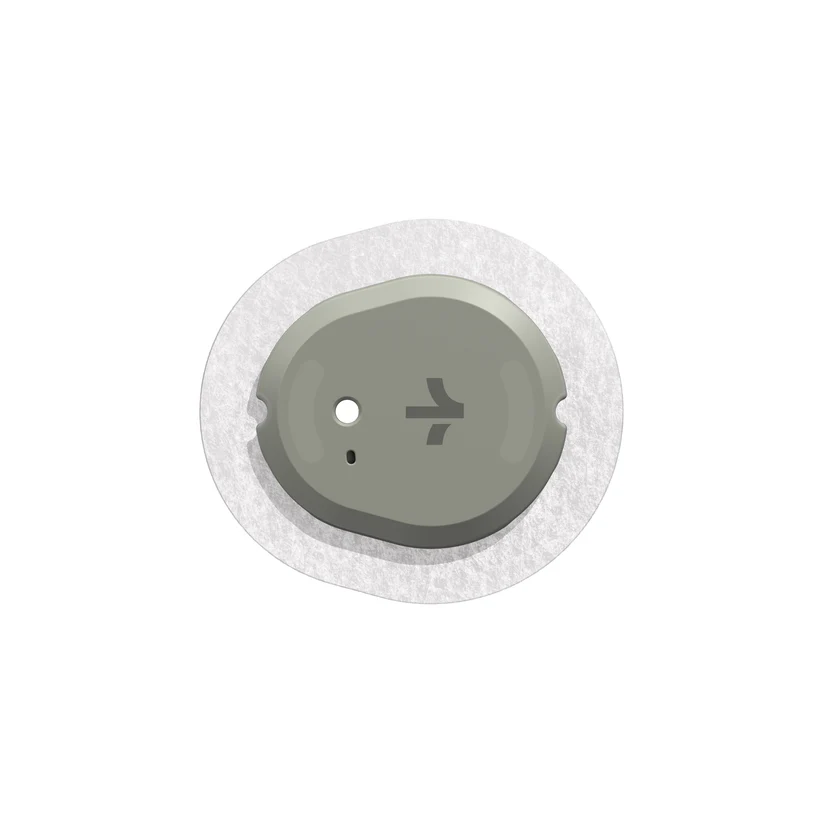

Understanding Glucose Levels

I love fitness and exercise. I always have. Movement feels natural to my body – I feel healthier, stronger, more centered, and less anxious when I’m active. Nutrition, on the other hand, is hard. I’m not a huge fan of eating or cooking. I find it annoying that I have to feed myself multiple times […]